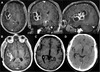

Extrapulmonary TB

Meningitis

- Imaging ⇒ enhancement of basilar meninges